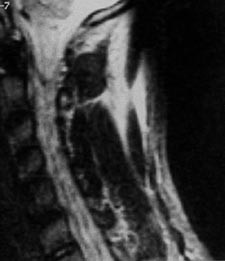

Pasienten falt om og hadde pustebesvær og kunne ikke bevege høyre sides ekstremiteter. Han ble brakt til lokalsykehus og man påviste hemothorax på høyre side, dette ble drenert. Nevrologisk undersøkelse viste høyresidig hemiparalyse og venstresidig bortfall av smerte- og temperatursans under C3-nivå. Vibrasjons- og leddsans ble ikke undersøkt i akuttfasen. Det ble gjort primær lukning av alle sår. Han fikk penicillin profylaktisk. Dagen etter innkomst ble det gjort MR som viste høysignalforandringer i medulla i C1/C2-nivå (fig 1, 2). Fem dager etter skaden var det øverste såret rødt og hovent. Suturene ble fjernet, og det tømte seg et hematom. Antibiotikum ble skiftet fra penicillin til cefotaksim. Pasienten var høyfebril og hadde stigende CRP-verdi. Dyrkingsprøve fra hematomet viste rikelig vekst av Enterobacter, og det ble igjen skiftet antibiotikum fra cefotaksim til imipenem. Ti dager etter skaden observerte man lekkasje av spinalvæske i såret, og etter 12 dager ble han overført til nevrokirugisk avdeling og operert dagen etter. Det ble gjort ny sårrevisjon samt laminektomi på C1 og C2 og duraplastikk. Man fant en fraktur på bakre atlasbue på høyre side. Duralesjonen var 5 mm lang. Videre var det tydelige kontusjonsforandringer i medulla svarende til duraskaden. C2-roten på høyre side var subtotalt overskåret.

Ved stikkskader i ryggmargen kommer nevrologiske utfall vanligvis akutt, men kan også opptre etter timer eller dager (6). Uansett er det viktig at mistanken vekkes selv med beskjedne ytre skader. Lekkasje av cerebrospinalvæske kan komme umiddelbart, men ikke nødvendigvis. Radiologisk diagnostikk er nyttig for å vurdere skadeomfanget. Konvensjonelle bilder samt CT vil avdekke både skjelettskader og eventuelle gjenværende fremmedlegemer. I tillegg vil CT spesielt kunne påvise intraspinal luft som tegn på penetrerende skade (7). CT vil også kunne påvise hematomer og traumatiske prolapser (7). MR gir imidlertid en mer detaljert oversikt over skader i bløtvev og spesielt i medulla (fig 1, 2). Man vil kunne se laserasjoner og skille mellom ødem og hematomer intraspinalt (5, 7). Slik er MR informativt både for terapi og prognose ved denne type skader. Vi vil likevel understreke betydningen av nøyaktig klinisk diagnostikk. Ut fra kliniske funn bør man raskt kunne fastslå skadenivå. I tillegg må man vurdere om andre organer kan være skadet (oesophagus, lunger, store halskar).